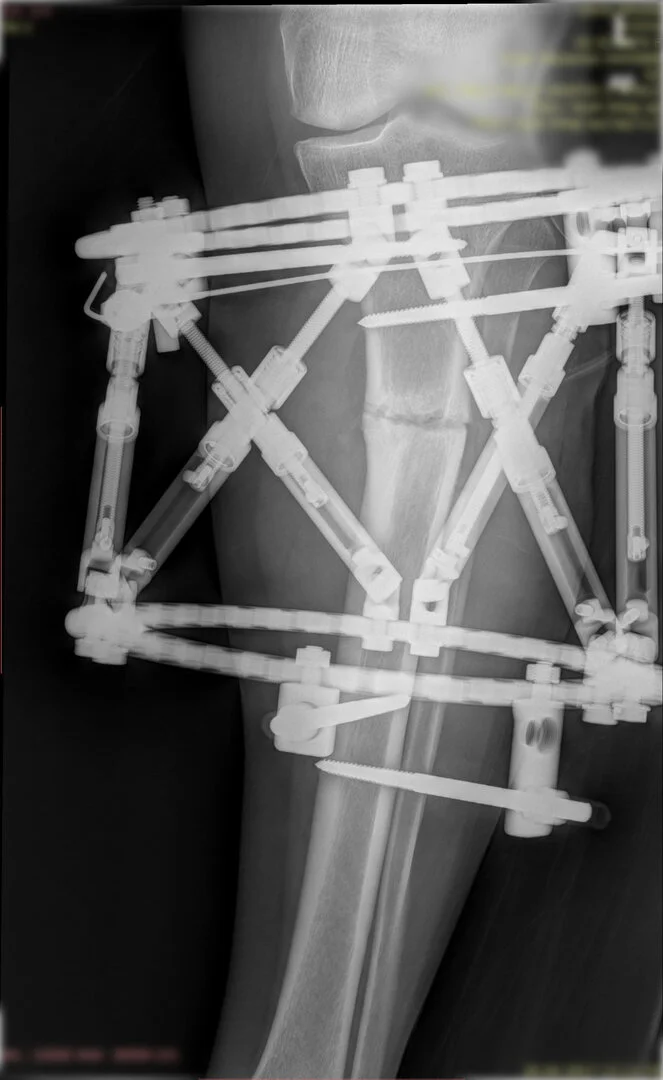

Deformitenin yeri ve miktarına bağlı olarak bilgisayar destekli sirküler eksternal fiksatör ile tedrici düzeltme yapılabilir. Bu sistemin avantajı düzeltme esnasında sistemle oynayarak yeni düzenlemeler yapmanıza izin vermesidir.

Bu ameliyat öncesi bir deformite analizi yapılıp hangi kemikte, normalden ne kadar sapma olduğu tespit edilir. Daha sonra bu kemiğe yine ostetomi yapılarak bu anormal sapma düzeltilir.  Bu düzeltme plak-vida veya intramedüller çivi ile akut olarak düzeltilebileceği gibi bilgisayar destekli sirküler eksternal fiksatör ile tedrici olarak ta yapılabilir. Hangi yöntemin hangi hasta için uygun olacağına hasta özelinde karar veriyoruz, ne tür cerrahi tedavi olması gerektiğini danışabilirsiniz.

Görüntüleri büyütmek için üzerine tıklayınız.